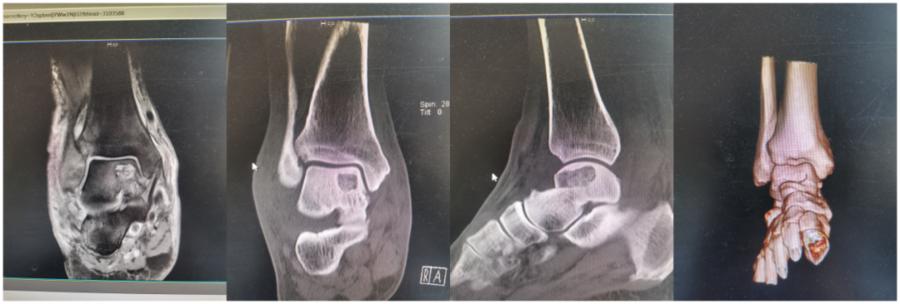

经过全面系统的专业检查,最终诊断为右踝滑膜炎、距骨囊肿、距骨软骨损伤。孙启彬认为可以行踝关节镜微创手术解决,患者欣然同意手术方案。

在孙启彬主任医师带领下,运动医学科团队为其成功实施了踝关节镜下前后联合入路全滑膜切除、距骨骨囊肿刮除、自体髂骨骨软骨移植。手术非常成功,术后患者几乎没有明显的肿胀疼痛,恢复良好,术后3天满意出院。